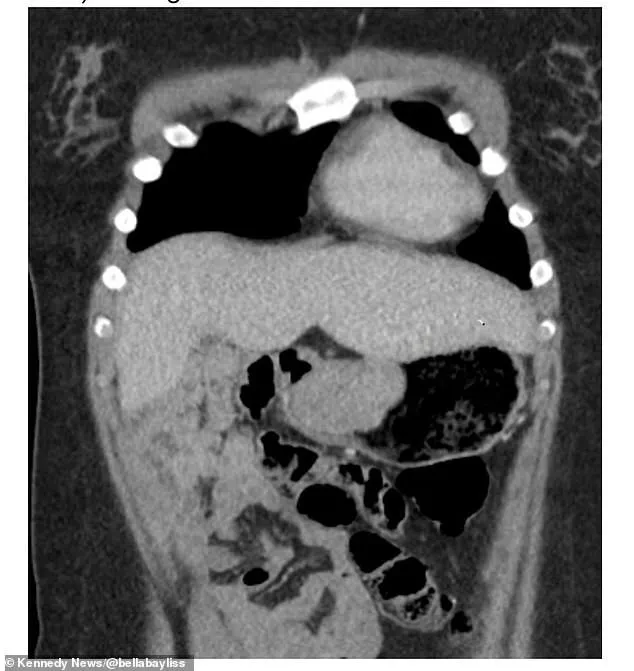

The results were revelatory: a 6cm gastrointestinal stromal tumor (GIST) had been growing in her stomach.

This rare form of cancer, which affects 10-15 people per million annually, accounts for just 1-2% of all gastrointestinal cancers.

In Bayliss’s case, surgeons had to remove 70% of her stomach to excise the tumor.